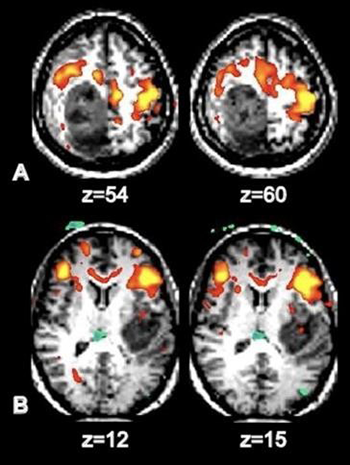

Figura 1: AJNR Am J Neuroradiol Oct 2013. Gráficos de Superficie de los RSN (red de estado de reposo):

La rRMf junto con la tractografía son dos herramientas importantes en el desarrollo de lo que se denomina proyecto del conectoma humano.

La rRMf ha proporcionado nuevas ideas sobre la arquitectura funcional del cerebro sano, en efecto se han identificado colecciones de regiones descriptas en el grafico anterior que tienen fluctuaciones BOLD espontáneas y sincrónicas. Si bien las aplicaciones clínicas de la rsRMf siguen siendo limitadas se están investigando muchas aplicaciones clínicas que incluyen la planificación pre quirúrgica para pacientes con tumores cerebrales y epilepsia. (Zhang y col, Kokkoonen y col.)

Figura 2: Identificación de áreas motora y del lenguaje en dos pacientes con glioblastoma:

A) desplazamiento anterior al tumor del área somatosensorial y B) desplazamiento anterior del área de Broca.

AJNR Am J Neuroradiol Oct 2013